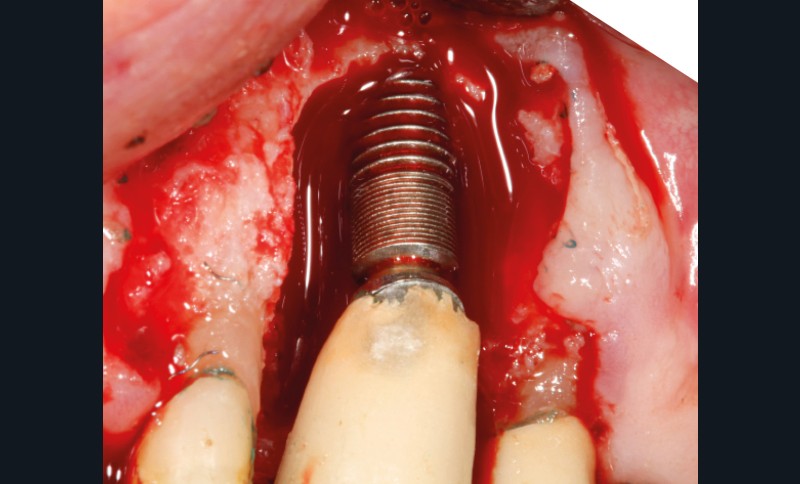

– Le laser Er-YAG, utilisé pour le nettoyage, est un laser avec un milieu actif composé d’yttrium, d’aluminium et de grenat dopé à l’erbium. Avec une longueur d’onde de 2 940 nm situé dans l’infrarouge, le laser Er-YAG est un laser à haute énergie, dont la lumière est absorbée dans l’eau et dans l’hydroxyapatite et qui ne pénètre pas profondément. Ceci permet de couper des tissus mous et des tissus durs, mais également de désorganiser le biofilm bactérie.

C’est un laser idéal pour le traitement chirurgical des péri-implantites. Il permet l’élimination du tissu de granulation à la surface de l’implant et de l’os ainsi qu’une décontamination mécanique par effet photoablatif.– Le laser Diode, utilisé pour la décontamination…